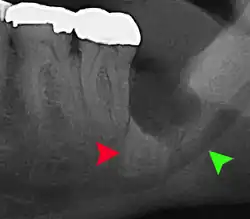

| Diagnostic method | Examination, x-ray |

If the tooth cannot be assessed with clinical exam alone, the diagnosis is made using either a panoramic radiograph or cone-beam CT. Where unerupted wisdom teeth still have eruption potential several predictors are used to determine the chance of the teeth becoming impacted. The ratio of space between the tooth crown length and the amount of space available, the angle of the teeth compared to the other teeth are the two most commonly used predictors, with the space ratio being the most accurate. Despite the capacity for movement into early adulthood, the likelihood that the tooth will become impacted can be predicted when the ratio of space available to the length of the crown of the tooth is under 1.[5]: 141

Long-term complications can include periodontal complications such as bone loss on the second molar following wisdom teeth removal. Bone loss as a complication after wisdom teeth removal is uncommon in the young but present in 43% of those of 25 years of age or older.[23] Injury to the inferior alveolar nerve resulting in numbness or partial numbness of the lower lip and chin has reported rates that vary widely from 0.04% to 5%.[23] The largest study is from a survey of 535 oral and maxillofacial surgeons in California, where a rate of 1:2,500 was reported.[26]

Coronectomy

Coronectomy is a procedure where the crown of the impacted wisdom tooth is removed, but the roots are intentionally left in place. It is indicated when there is no disease of the dental pulp or infection around the crown of the tooth, and there is a high risk of inferior alveolar nerve injury.[32]